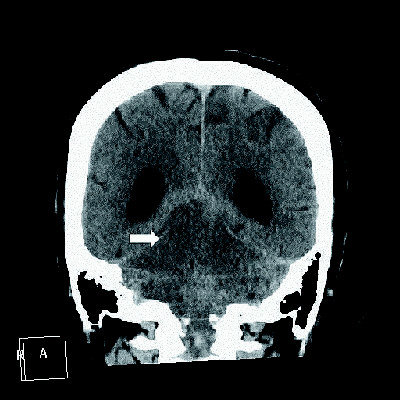

箭頭指發生梗塞受損的腦幹,病患常常已陷入昏迷狀態。(圖:莊毓民醫師提供May 03, 2011)

腦幹是生命中樞,掌管呼吸心跳血壓等,嚴重的腦幹中風,死亡率可能到達八成。如此致命的腦幹中風,最初表現竟可能只是突發性眩暈。